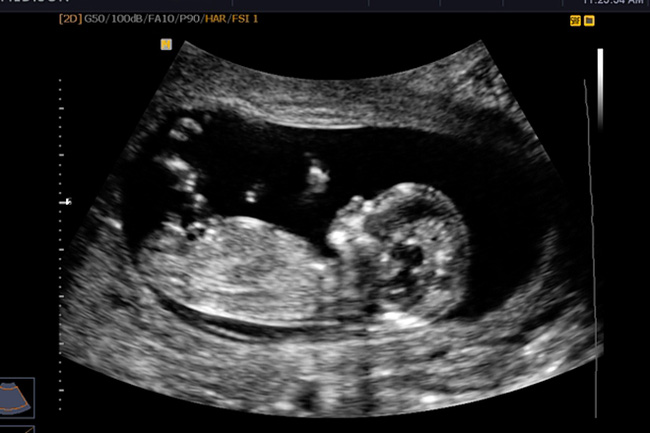

Chưa có nghiên cứu nào khẳng định việc siêu âm thai có ảnh hưởng không tốt tới thai nhi. (Ảnh minh hoạ)

Thực tế chưa có nghiên cứu nào khẳng định việc siêu âm có ảnh hưởng không tốt tới thai nhi. Tuy nhiên mẹ bầu cũng không vì thế mà lạm dụng vì có những vụng rất nhạy cảm với sóng siêu âm như mắt hoặc tuyến sinh dục.